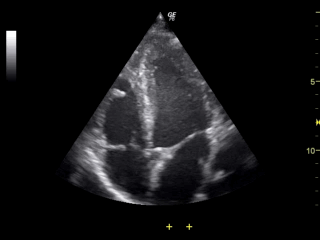

Indeed, one of the problem of x-rays is that they are dangerous. Due to their high energy level, they can ionize particles and modify the chemical properties of atoms. As a consequence they can break down DNA or, even worst, kill cells, which leads to pretty nasty consequences when their emissions are not properly controlled. Each time a doctor requests a CT exam, he is taking a risk. He has to weight the benefit of exposing his patient to dangerous ionizing rays versus the risk of not knowing exactly what is wrong with him. But fret not! X-rays are not the only mean to this end. Other type of medical imaging exists that are not inherently dangerous like Magnetic Resonance and Ultrasound.

Ultrasound of a human heart.